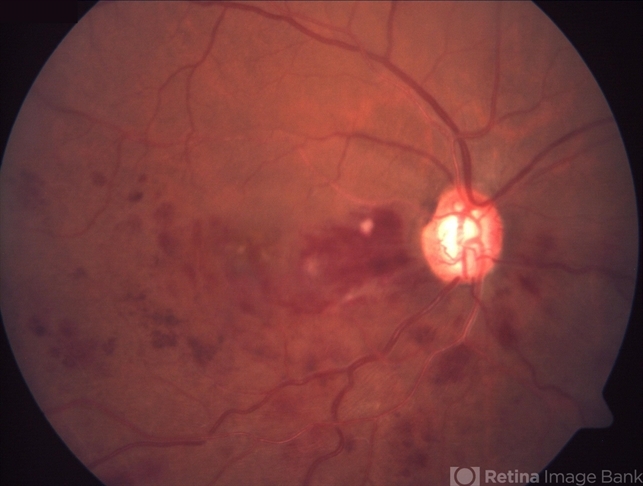

- Hemicentral Retinal Vein Occlusion

- Fundus photograph of a 67 year-old male showing flame-shaped and blot hemorrhages in the inferior hemiretina.